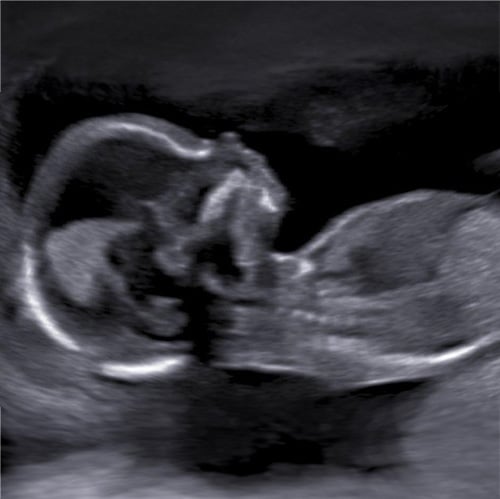

Een 2D echo maakt een dun plakje van jullie kindje, dit kan in de lengte zijn, dan zie je het kindje mooi op de rug liggen of een dwars doorsnede. Je kijkt dan als het ware door het kindje heen en kunt de binnenkant van de baby bekijken. Bij een 2D echo zie je het kindje in het zwart-wit beeld. De 2D beelden worden ook bij de medische echo’s gebruikt voor het meten van de groei en het beoordelen van het welzijn van het kindje.